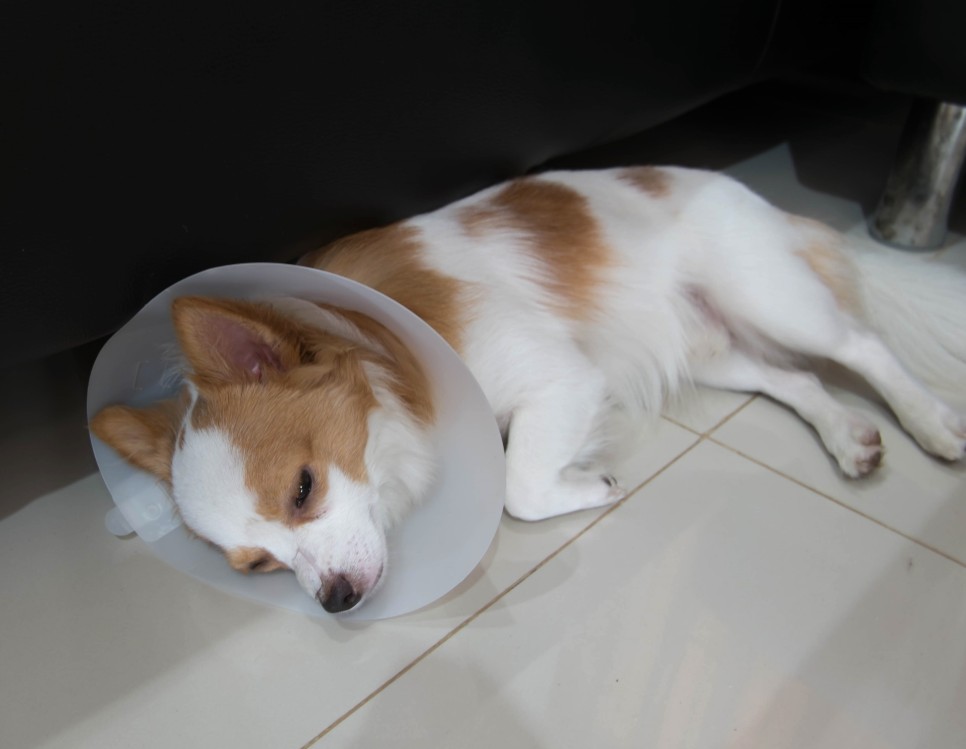

강아지 심부전 치료 케이스 11세의 암사페이 메리(가명)는 흉수와 복수를 주증하고 해말동물병원에 긴급 내원한 환자입니다.

폐 고혈압과 우심부전으로 응급 내원한 강아지 메리는 해마루 중환자실에서 집중치료를 받은 후 흉수, 복수 및 호흡상태가 개선되어 무사히 퇴원할 수 있었습니다.